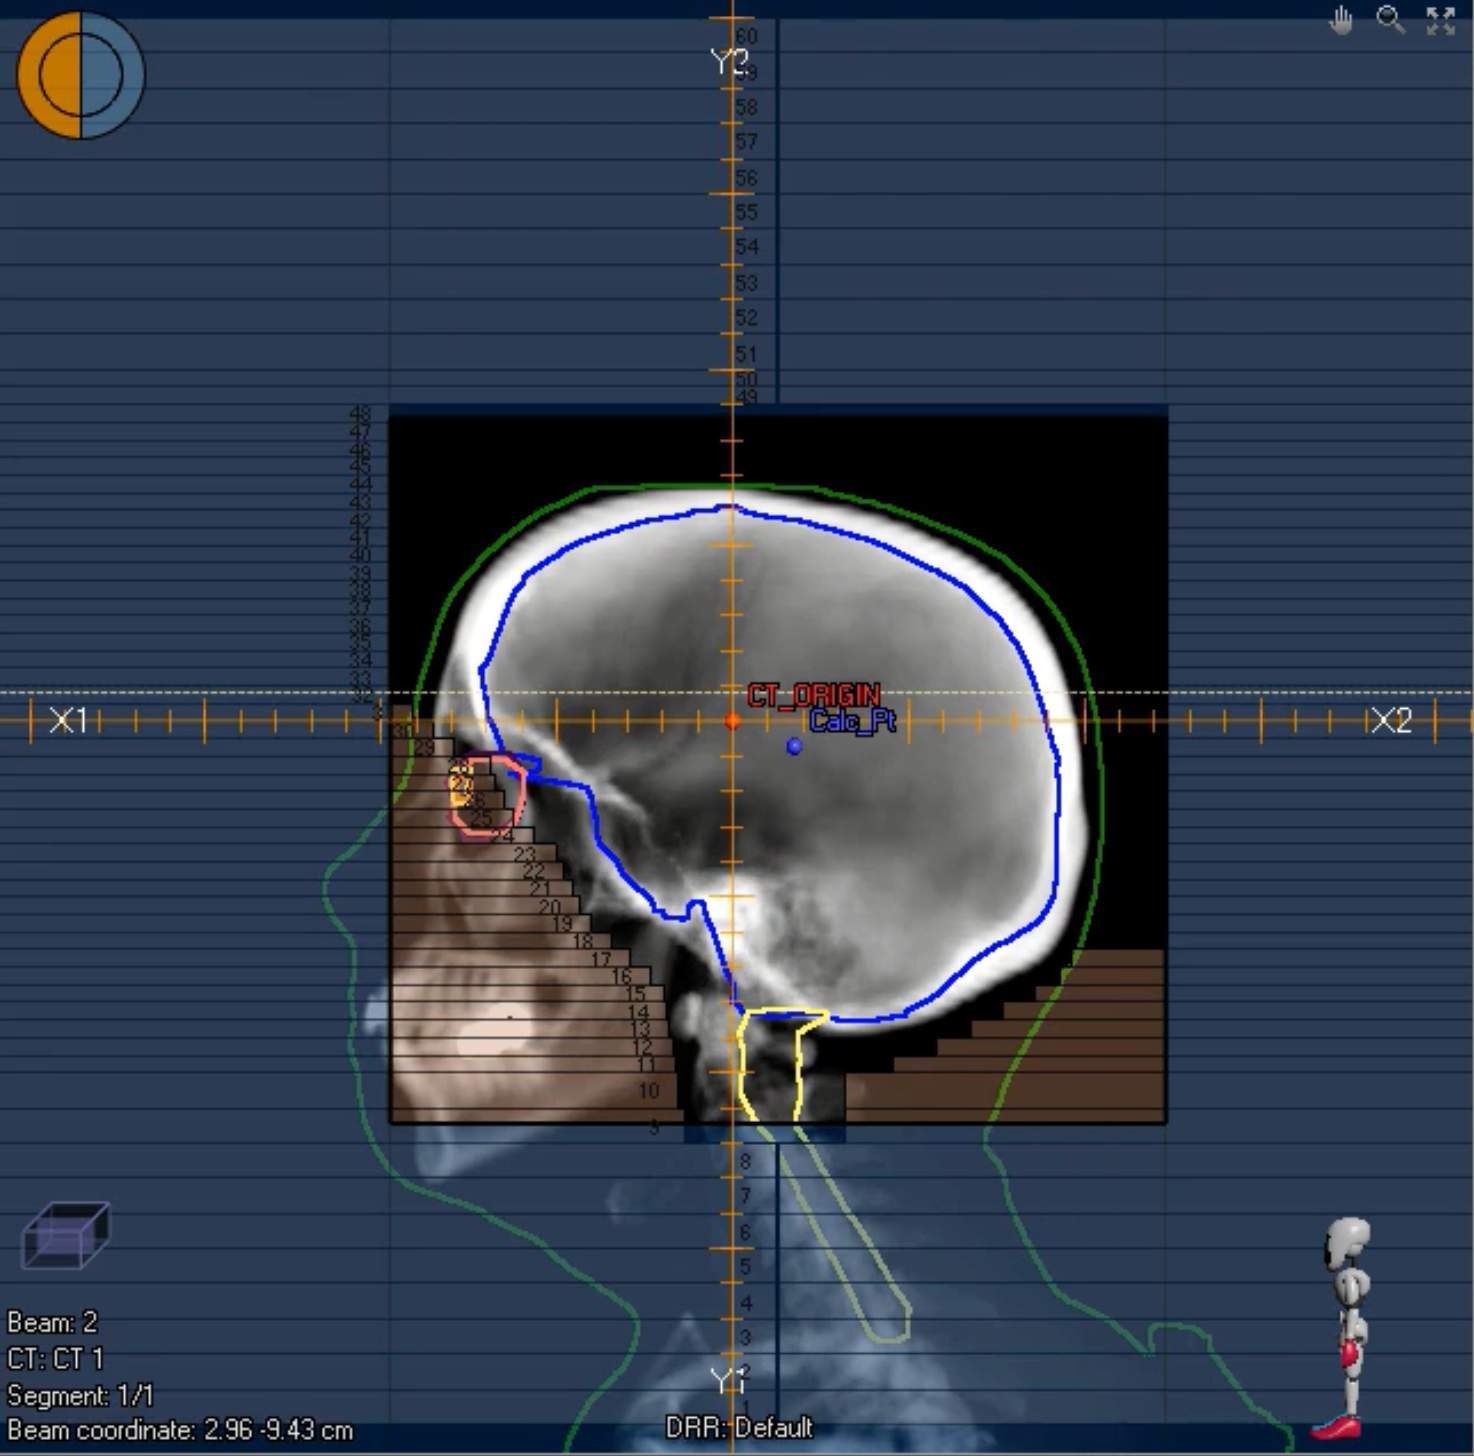

In some instances, you may want to spare the lenses. One technique to achieve this is to rotate the gantry approximately 5 degrees (R_Lat = 275 degrees, L_Lat = 85 degrees) to match the divergence behind the lenses. This is illustrated on the left.

Field Blocking (Non-Scalp Sparing)

Standard field blocking for WBRT is shown in the image. While setting the field borders, keep the following in mind:

- Flash superiorly (for non-scalp sparing plans), anteriorly above the orbits/eyebrows, and posteriorly above the nape of the neck

- Inferior border: typically C1, though this may vary depending on the clinical scenario

- Block eyes and nasopharynx—bring the anterior border to the vertebral body inferiorly

- Ensure adequate coverage of the entire brain, particularly the temporal lobes and cribriform plate